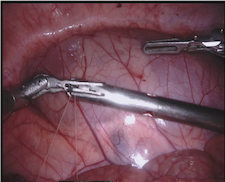

Our challenge was made up of 3 sub-problems. The first was binary instrument segmentation, where each frame was separated into da Vinci Xi instruments and a background class, which contained an ultrasound probe, surgical clips and porcine tissues. The second task was instrument part segmentation, where we scored the participants on whether they could correctly segment each articulating part of the instrument (see Fig. 3). Our final task was to segment and classify the instruments (see Fig. 4).

We provided the first 225 frames of 8 sequences as training data and kept the last 75 frames of those 8 sequences as test data. 2 of the full 300 frame sequences were kept as test sequences. Test labels were kept hidden from the participants. Our datasets contain 7 different robotic surgical instruments. The Large Needle Driver, Prograsp Forceps, Monopolar Curved Scissors, Cadiere Forceps, Bipolar Forceps, Vessel Sealer and additionally a drop-in ultrasound probe, which is typically held in the jaws of the Prograsp Forceps instrument. Samples from the training datasets are depicted in Fig. 2 and examples of the different instrument types are shown in Figure 3 and 4.